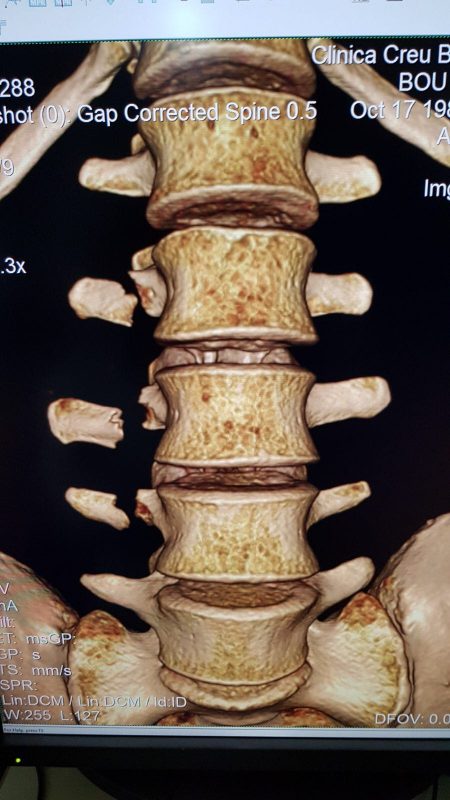

Following the painful accident Bou, who has already claimed five wins in the 2018 X-Trial Championship, was rushed to hospital. Team doctor Joaquim Terricabras diagnosed fractures of ‘the right apophysis transverse of the lumbar vertebrae L2-L3-L4’.